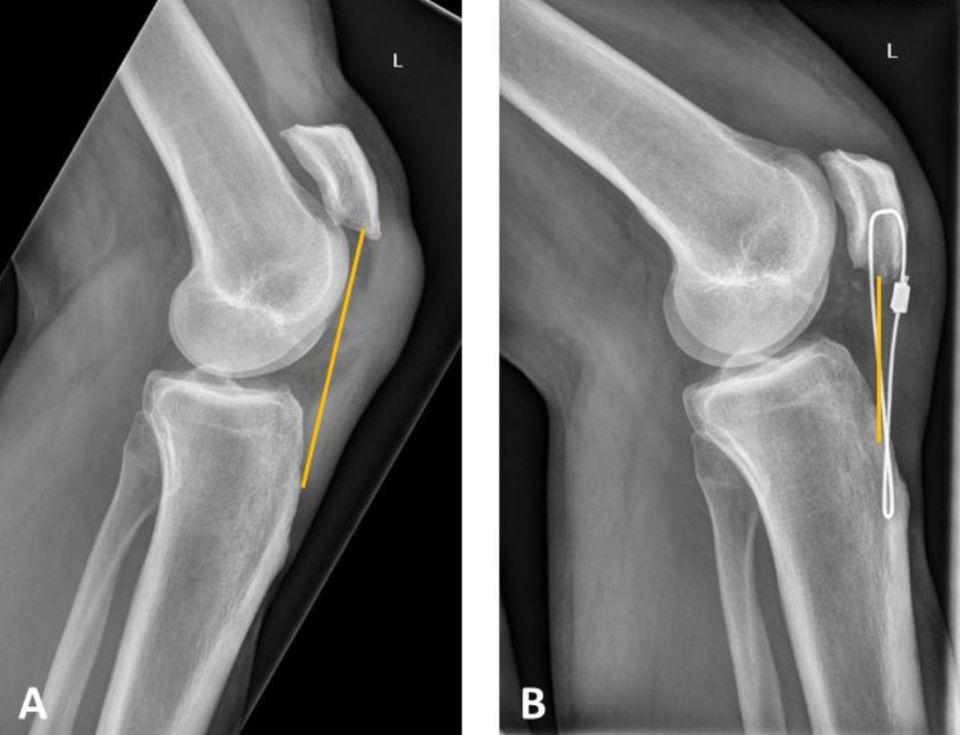

Einer der häufigsten Gründe für die Ruptur der Quadricepssehne ist der Sturz auf das gebeugte Knie. Im Rahmen der arthroskopisch durchgeführten Operation wird die gerissene Sehne mit Hilfe einer Sehnennaht und oftmals zusätzlich einem Nahtanker fixiert.

Sehr viel häufiger reißt die Achillessehne, die die Wade hinten mit der Ferse verbindet; dieser faserige Strang ist schmaler und länger als. Im Rahmen der arthroskopisch durchgeführten Operation wird die gerissene Sehne mit Hilfe einer Sehnennaht und oftmals zusätzlich einem Nahtanker fixiert. die Dein Knie in einem bestimmten Winkel hält und nahezu die volle Belastung des Beins im Alltag ermöglicht.